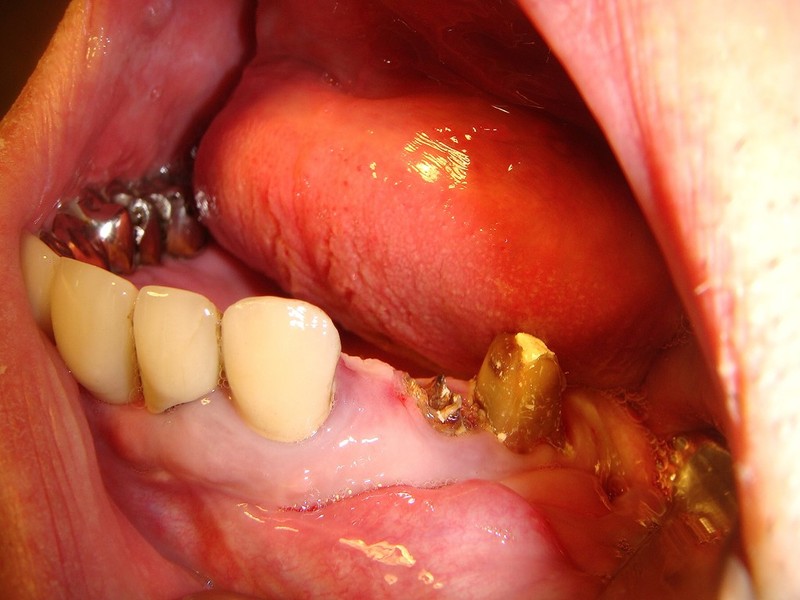

Estrazione radice e inmnesto Epitelio-Connettivale

Estrazione di un canino incluso e contestuale inserimenti di impianto e innesto osso eterologo